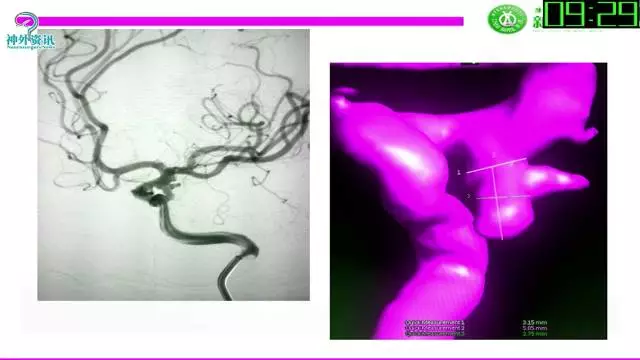

今天为大家分享的是“强生医疗CNV-神经介入专栏”第三十六期,由重庆第三军医大学附属新桥医院神经外科刘俊带来的“Galaxy弹簧圈在不规则动脉瘤中的临床应用”精彩讲课视频及PPT,欢迎观看。文章仅代表作者个人观点,如有不同见解,欢迎同道斧正!